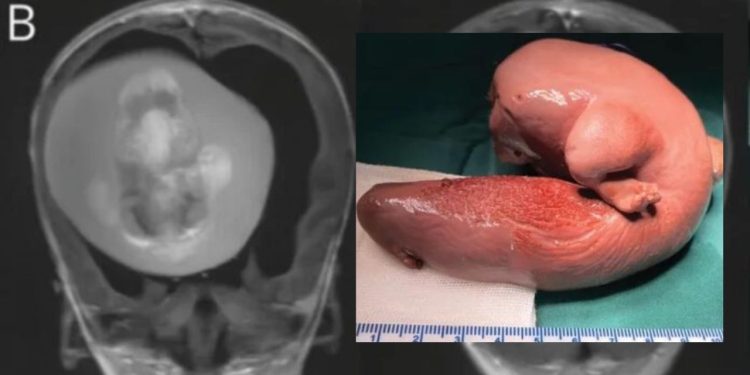

Uma criança chinesa de 1 ano passou por uma cirurgia delicada para retirar o feto de seu irmão gêmeo do cérebro. O embrião ficou alojado no crânio da criança enquanto ambos se desenvolviam no útero da mãe, em uma condição extremamente rara, conhecida como fetus in fetu (gêmeo parasitário).

Médicos do Huashan Hospital, ligado à Universidade Fudan, na revista Neurology, da Academia Americana de Neurologia, registraram o caso.

De acordo com os médicos responsáveis pelo procedimento, o feto foi descoberto quando os pais da menina procuraram o hospital para investigar porque a criança tinha o volume da cabeça aumentado e apresentava dificuldades motoras.